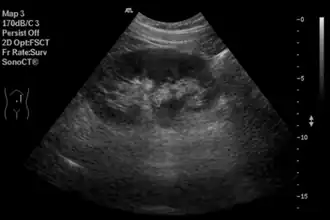

El ultrasonido médico es una técnica de diagnóstico por imagen médica basada en ultrasonido que se utiliza para visualizar músculos, tendones y muchos órganos internos para capturar su tamaño, estructura y cualquier lesión patológica con imágenes tomográficas en tiempo real.[13] Es de especial utilidad en este sector porque permite observar imágenes del interior del cuerpo en forma innocua y simple, por lo cual se le conoce como el "fonendoscopio moderno". Tal como se aplica actualmente en el campo de la medicina, la ecografía realizada adecuadamente no presenta riesgos conocidos para el paciente. La ecografía no utiliza radiación ionizante, y los niveles de potencia utilizados para la obtención de imágenes son demasiado bajos para causar efectos adversos de calentamiento o presión en los tejidos.[14]

Sistema digestivo

En la ecografía abdominal, se forman imágenes de los órganos sólidos del abdomen como el páncreas, la aorta, la vena cava inferior, el hígado, la vesícula biliar, los conductos biliares, los riñones y el bazo. Las ondas sonoras son bloqueadas por el gas en el intestino y atenuadas en diferentes grados de grasa, por lo que hay capacidades de diagnóstico limitadas en esta área. El apéndice a veces se puede ver cuando se inflama.[20]